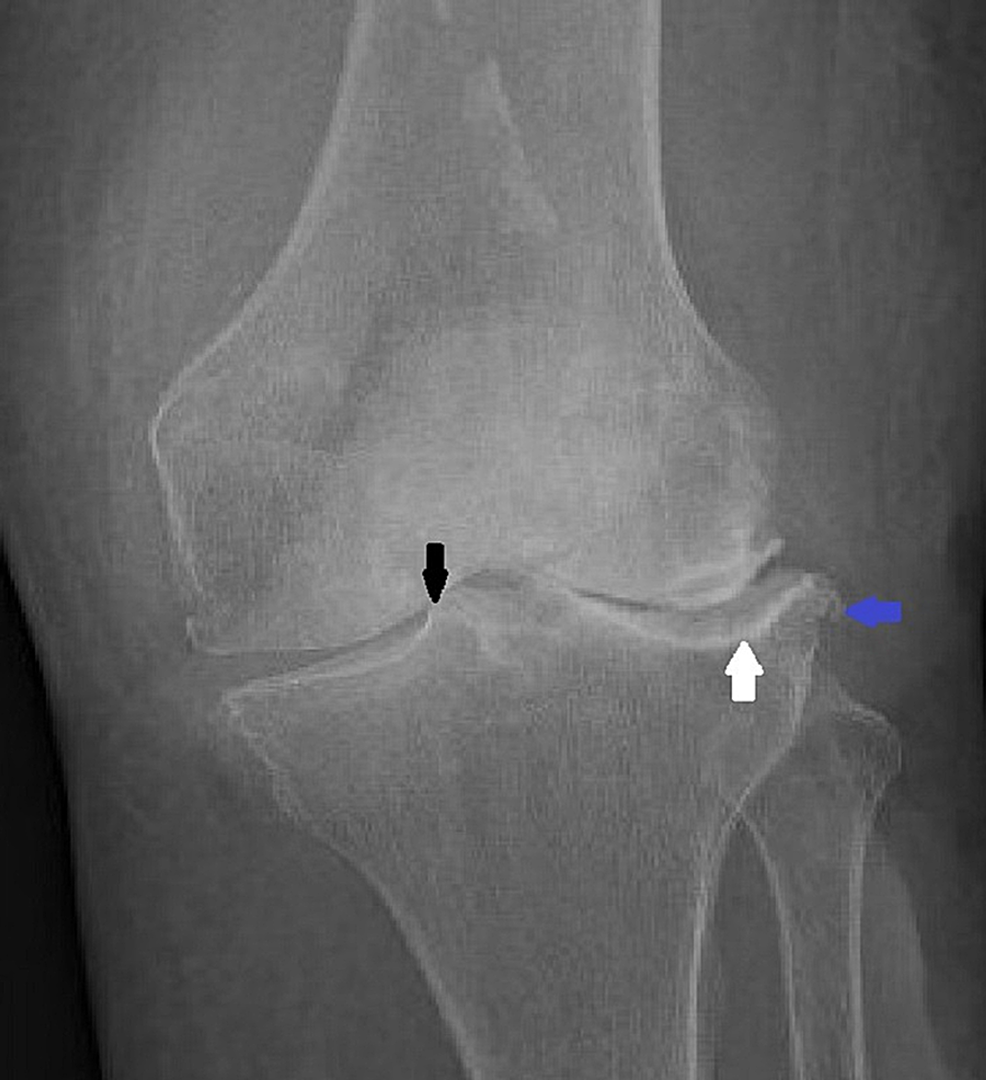

From www.cureus.com

A Rare Case of Septic Knee Arthritis Caused by Clostridium perfringens in a Patient With Scraped Knee Sepsis 1 patients with septic arthritis may present with. Infection is usually a result of bacteria. septic arthritis is a painful infection in a joint that can come from germs that travel through your bloodstream from. remember that time you shrugged off a seemingly harmless scrape on your knee? if the infection that caused your septic arthritis is. Scraped Knee Sepsis.